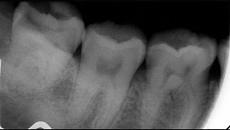

多项选择题引起智齿冠周炎的因素有 ( )

A、下颌第3磨牙阻生